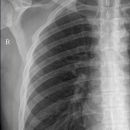

Rippenfrakturen

Standardaufnahmen sind die Thorax ap (Begleitverletzungen!) – und die Aufnahme des knöchernen Hemithorax bzw. des oberen und unteren knöchernen Hemithorax.

Cave: Rippenfrakturen sind die häufigste Skelettverletzung überhaupt! Röntgenologisch werden nur etwa 70% der Rippenfrakturen nachgewiesen! Bei Rippenserienfrakturen wird das Ausmaß meist unterschätzt. Klinische Diagnose, bis auf wenige Ausnahmen (massive Dislokation, schwere pulmonale Läsionen) konservative Therapie! Wichtiger ist der Nachweis begleitender Komplikationen!

Aufhellungs- oder Verdichtungslinie (meist vertikal oder schräg verlaufend) Konturunterbrechung bzw. Stufenbildung insbesondere der Rippenoberkante.

Einzelfraktur, Serienfrakturen (2,3) (>2 benachbarte Rippen), Stückfrakturen

Lokalisation

meist mittleres oder hinteres Drittel der 4.-9. Rippe.